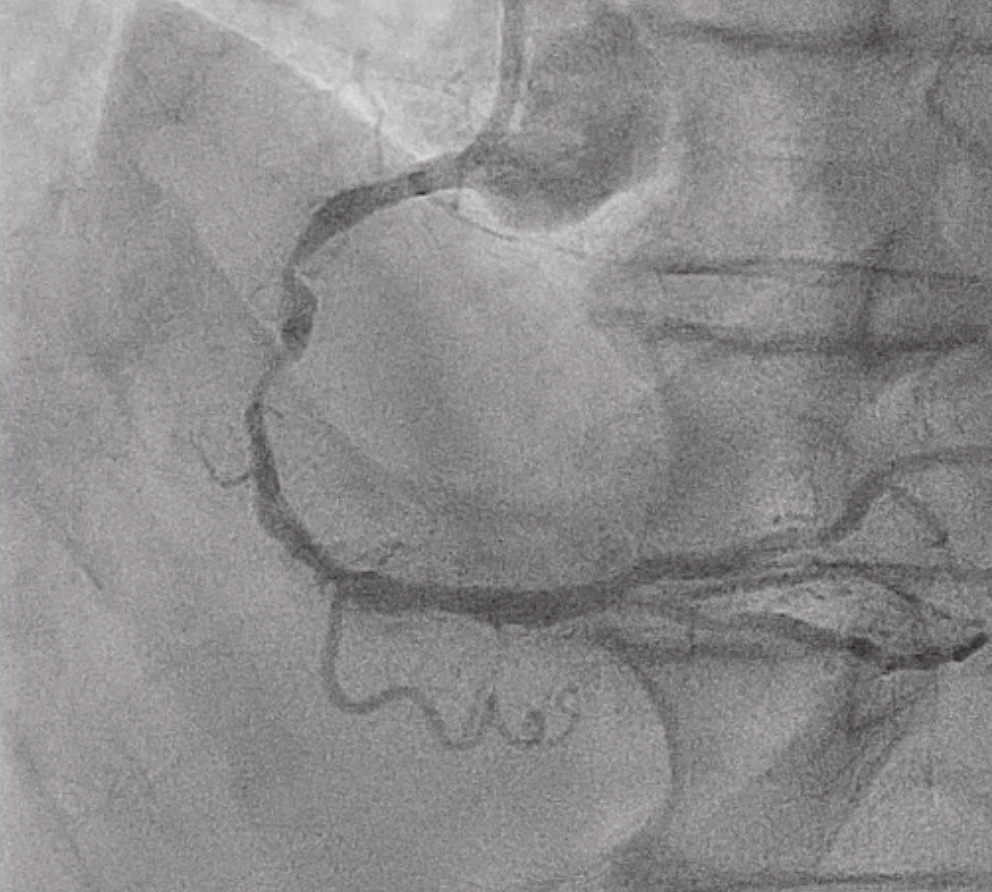

Coronary angiography showed a patent left main artery. The LAD had luminal irregularity with diffuse 70–90% stenosis from proximal to distal segments (Medina 1,0,1) involving the first diagonal branch and 70–80% tubular stenosis at the D1 ostium. The LCX showed prior stenting from proximal LCX to OM1 without in-stent restenosis and additional 50–60% stenosis at mid to distal segments. The RCA revealed diffuse eccentric 70–95% stenosis with severe calcification from proximal to distal segment.

Right distal radial artery was used for access with a 6 Fr JR 3.5 guiding catheter. Anticoagulation was given to keep ACT >250 seconds and dual antiplatelet therapy was continued. A Runthrough wire crossed the diffusely calcified RCA lesion from proximal to distal. Sequential predilation with 2.0–3.0 mm non-compliant balloons was performed to assess vessel compliance.IVUS showed heavy concentric calcification with a minimal lumen area of 3.3 mm©÷. Calcium modification was done using a 4.0 ¡¿ 12 mm intravascular lithotripsy balloon with a total of 70 pulses, achieving good luminal expansion. Two drug-eluting stents were then implanted: 3.5 ¡¿ 50 mm at mid–distal RCA and 4.0 ¡¿ 24 mm at proximal–mid RCA, followed by high-pressure post-dilation up to 20 atm.After optimization, angiography revealed Ellis class II–III perforation at mid RCA. A 7 Fr system with Guideliner support was used for bailout. A 3.5 ¡¿ 19 mm covered stent was deployed to seal the perforation, followed by additional dilation. Because of residual contrast leakage, another 3.5 ¡¿ 16 mm covered stent was placed at proximal RCA, achieving complete sealing.Final IVUS confirmed good stent expansion and apposition. Angiography showed less than 30% residual stenosis with TIMI 3 flow.